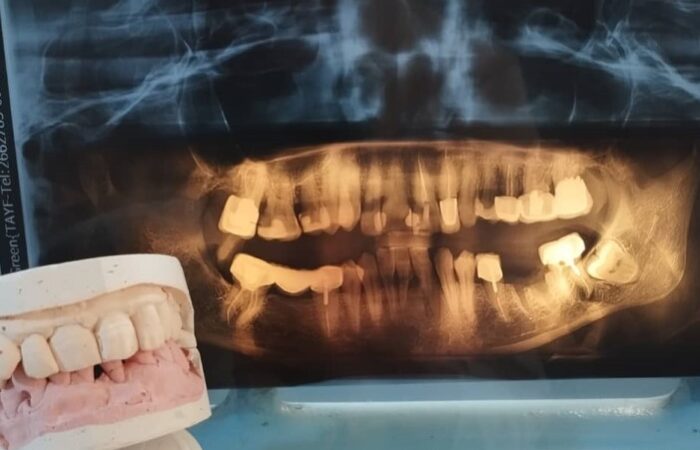

الطعوم العظمية السنية – الأنواع والبدائل

الطعوم العظمية السنية – الاستطبابات، الخصائص والآثار الجانبية

الأكياس سنّية المنشأ – الأنواع، التشخيص والأسباب

الأجهزة السنية المتحركة الكاملة – الميزات، السلبيات وما هي مضاعفاتها؟

الأجهزة السنية المتحركة الجزئية – المكونات والاستطبابات